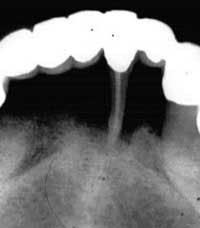

The plaintiff was a 55-year-old school teacher who had been under the almost continuous care of a general dentist in Florida from 1963 until 1995. During her 32-year course of treatment by the defendant, the plaintiff diligently and almost religiously returned to the office for periodic prophylaxes. These cleanings were performed by the defendant and not by a dental hygienist. In 1970, the defendant took a full-mouth series of dental X-rays, as well as taking bitewing X-rays at many of the patient's cleaning visits.

The patient was never told about the onset or progression of periodontal disease until December 1995, when she developed a periodontal abscess and the defendant made a new full-mouth series of X-rays. Even then, the dentist didn't tell her about her periodontal disease, but, instead, referred her to a periodontist who "had to tell her the bad news." The plaintiff lost several teeth and required four quadrants of periodontal surgery.

This case was settled during the presuit investigation period for the defendant's policy limits of $100,000.

(Used with permission from The Dentalaw Group, Boyd Shepherd, DDS, J.D., 16514 Canyon Chase Dr., Suite 200, Houston, Texas 77095)